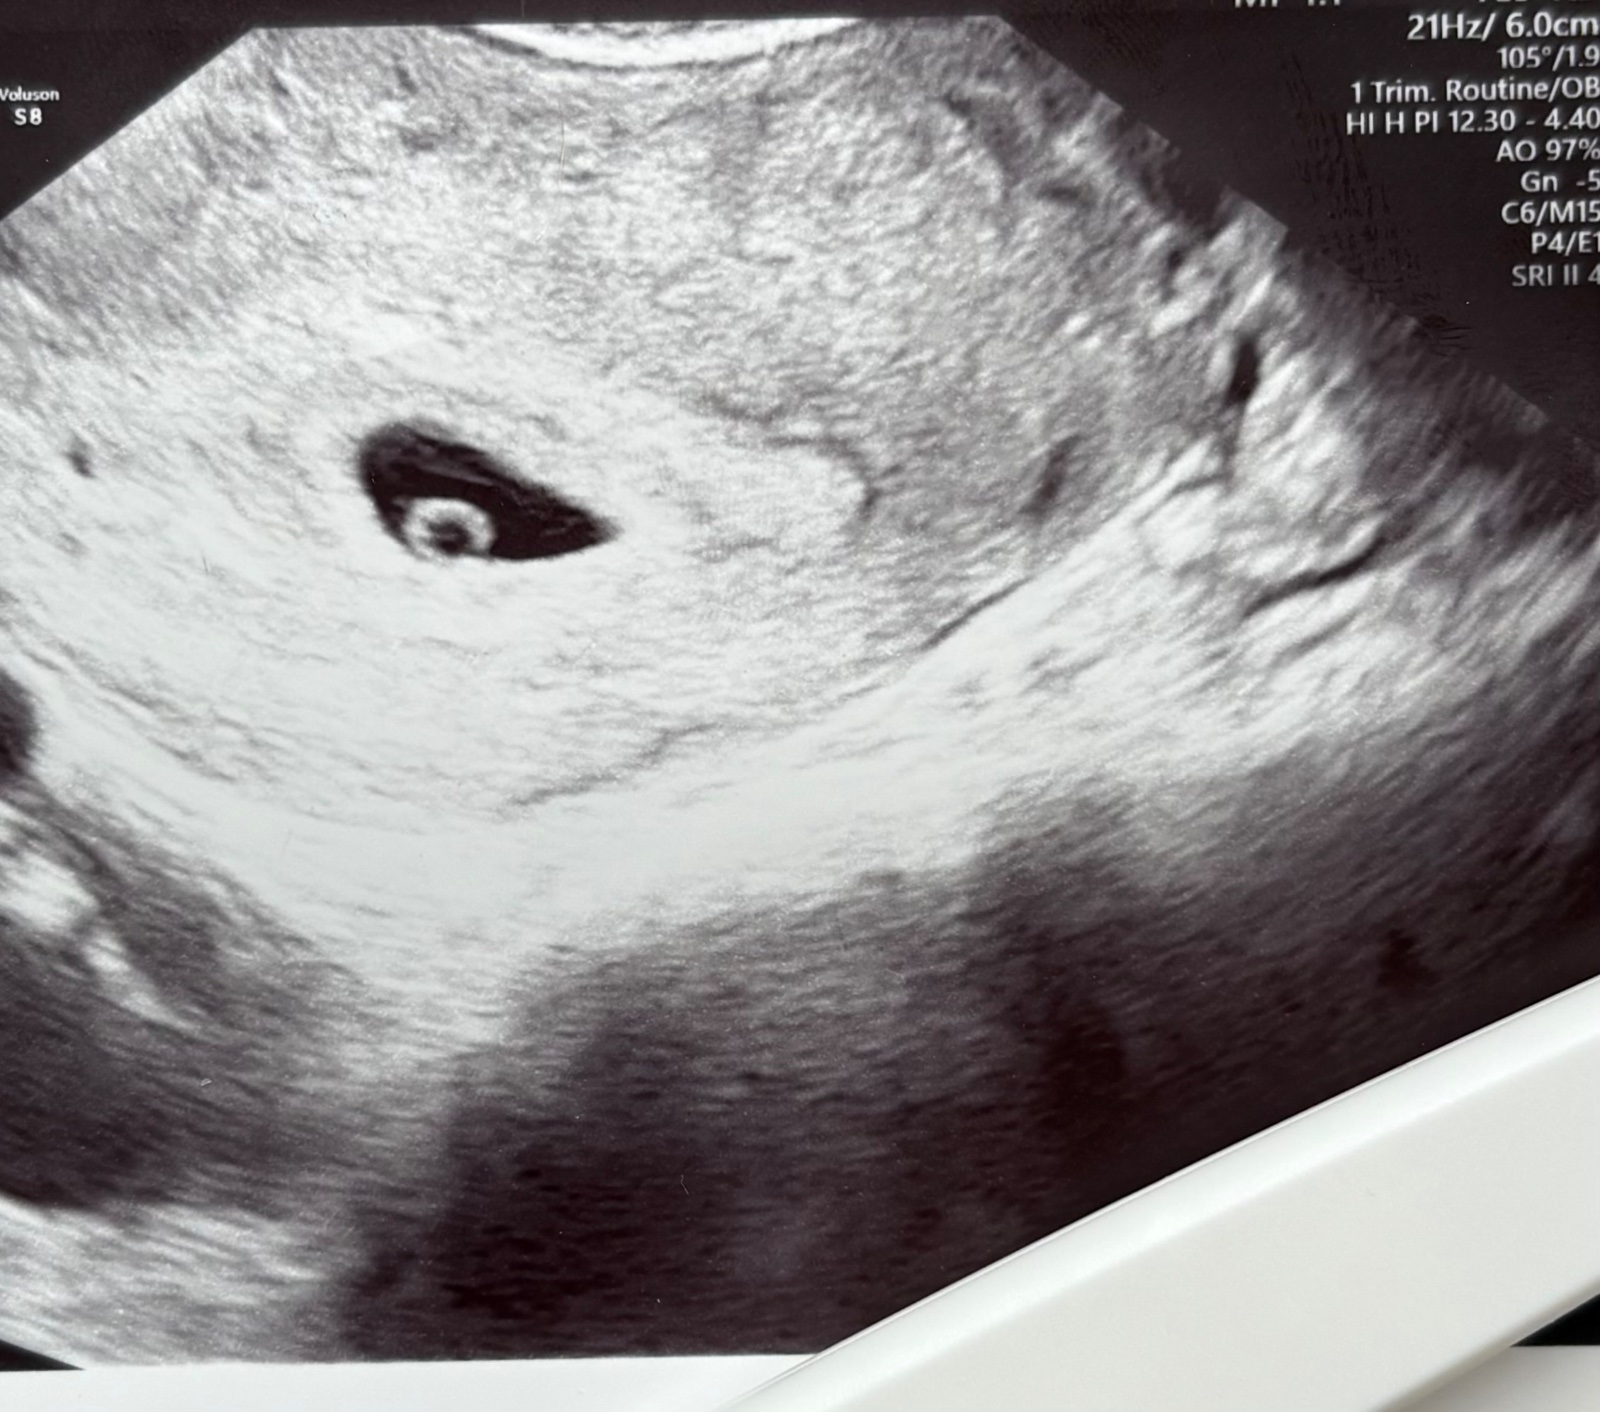

Ahojte, bola som minuly týždeň u dr. na ultrazvuku. Vraj som asi 5-6tyzden, keďže mám nepravidelný cyklus.

@luci2499 este je to skoro, podla mna je to tak 5/6 tt max a za mna to vyzera dobre, uvidis o tych 10 dni, tue skore usg je tazke presne urcit. Ber to tak, ze priroda dopriala a bude to dobre. Ja som mala v 8tt tiez taku gulicku vacsiu a v nej to blikajuce srdiecko. Povedala by som, ze u Teba to bude rovnako